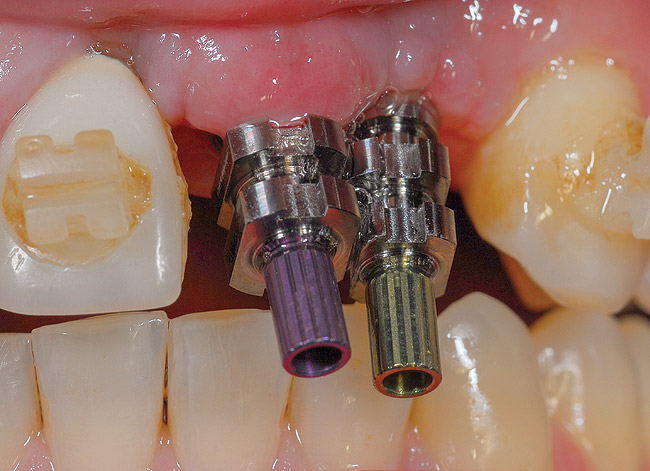

Figure 28  (Case 3) Fix level impression copings in place. Note mesial angulation of No. 9 implant, which compromises emergence profile. This is a common occurrence in compromised bone due to the more crestal position of the incisive foramen.

Figure 28

Figure 29  (Case 3) Proximity of impression copings.

Figure 29